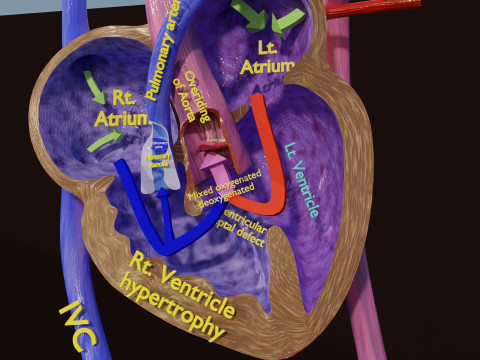

The model meshes include adult circulation versus circulation in Tetralogy of Fallot (TAF), arrow labels and text labels. The blood flow in a patient with Tetralogy of Fallot is outlined in this model. To contrast it to normal blood circulation a separate model of normal circulation is included. The Tetralogy of Fallot (OVER RIDING OF AORTA, PUL STENOSIS, VENTRICULAR SEPTAL DEFECT, RIGHT VENTRICULAR HYPERTROPHY), fossa, ligament teres , venosus, and arteriosus are duly depicted with proper labelling and blood flow directional arrows. Excellent model for teaching, demonstration and knowlegde of human body. The models include both procedural and image textures blend files separately. The texture file include diffuse, roughness and normal png and jpeg based on non overlapping UV maps.